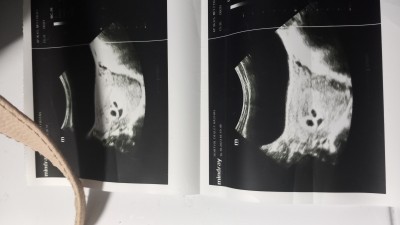

Ultrasan görüntüsünü bilen yada anlayan yorumlayabilirmi canlar

Tek yumurtamı çift yumurtamı teşekkürler simdiden

Üçüz mü canım

İkiz canım

Bence çift yumurta

Ben tek yumurta olarak görüyorum ama doktor falan değilim tabiki kesin konusamam :) sağlıkla gelsinler